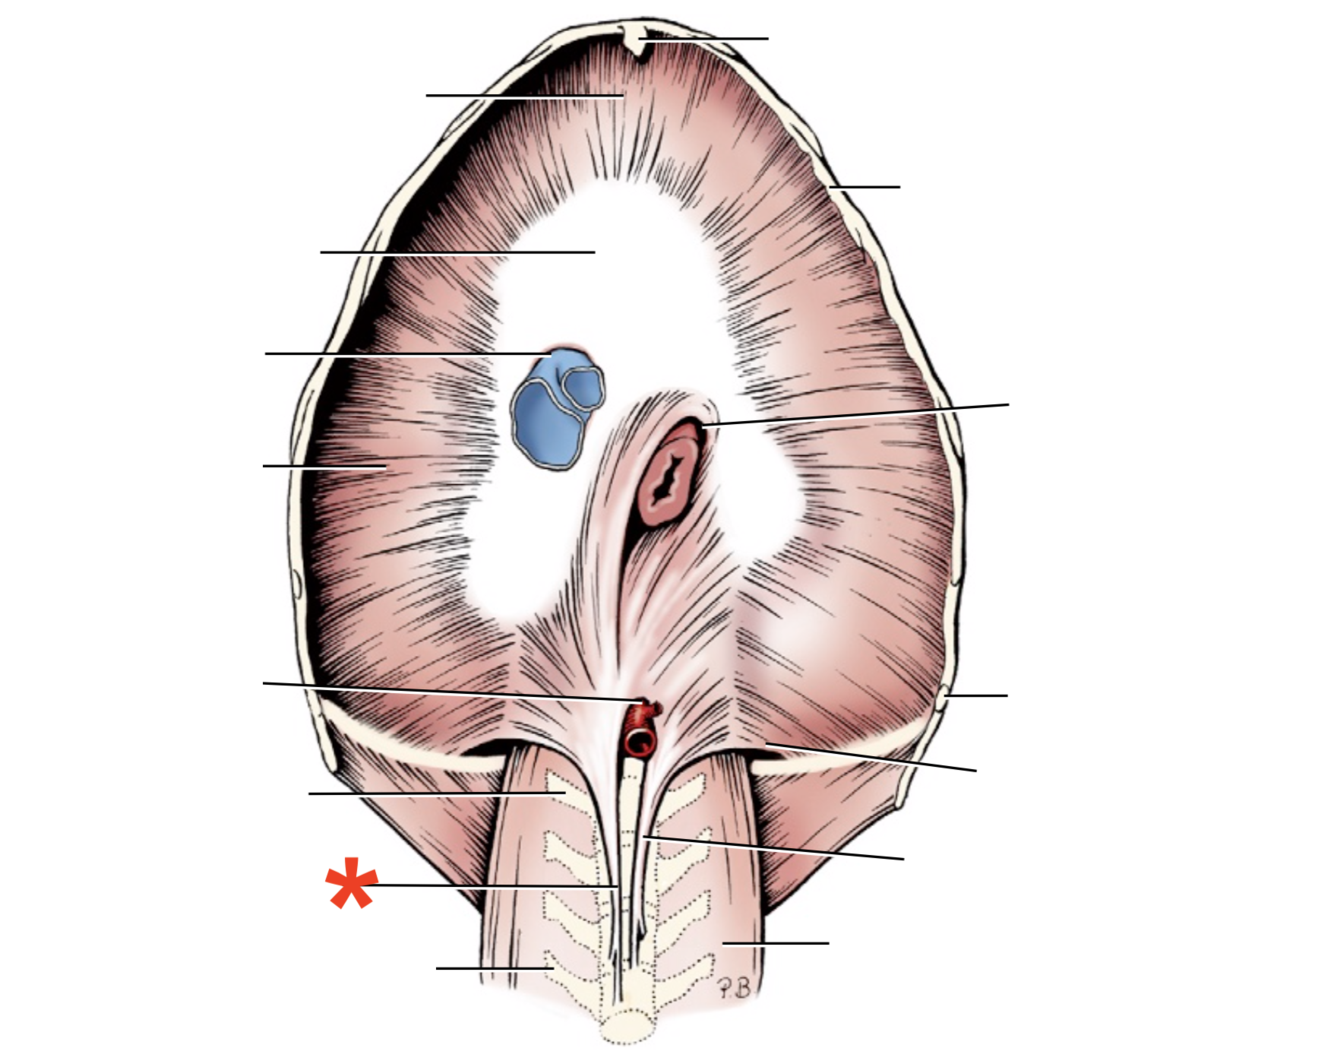

Name given to the most cranial part of the diaphragm.

Cupula Diaphragmatis

Q

Pars sternalis

Q

Foramen vena cavae

Q

Pars costalis

Q

Hiatus aorticus

Q

Arcus lumbocostalis

Q

Hiatus oesophagus

Q

Crus sinistrum

Q

Crus dextrum

Q

Centrum tendineum

Q

Corona muscularis